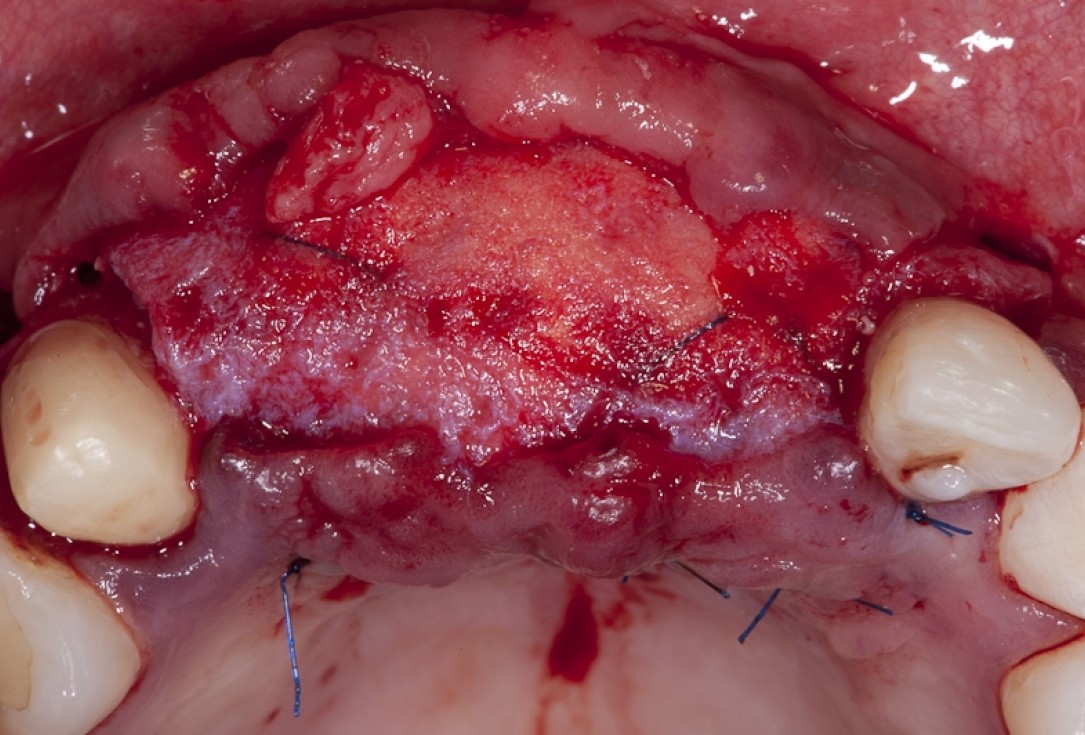

04/17 - Full flap elevation and severe hard tissue exposure

Block augmentation with maxgraft® block & mucoderm® - Dr. K. Chmielewski